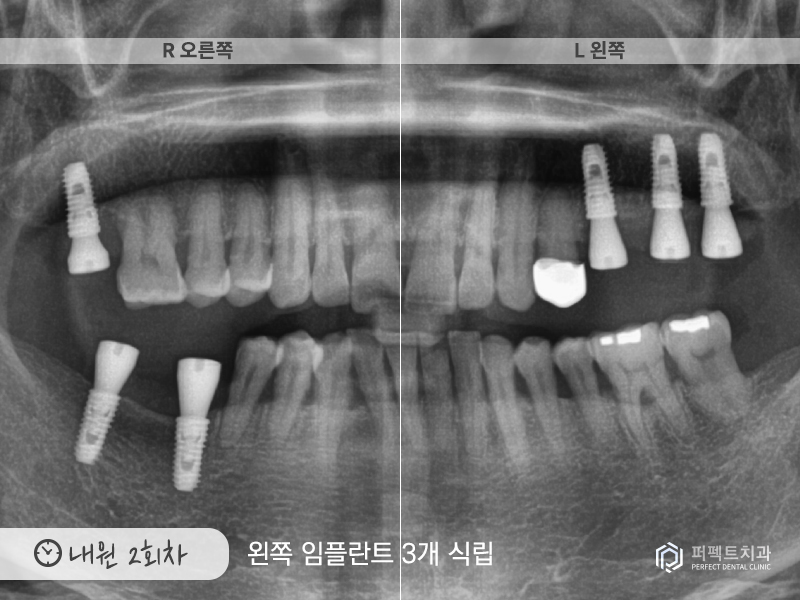

두번째 내원하신 날에는 왼쪽 임플란트 3개를 식립하였습니다.

내원 3회

그리고 3번째 내원하신 날에는 실을 제거하고 지르코니아 크라운까지 진행을 하였습니다.